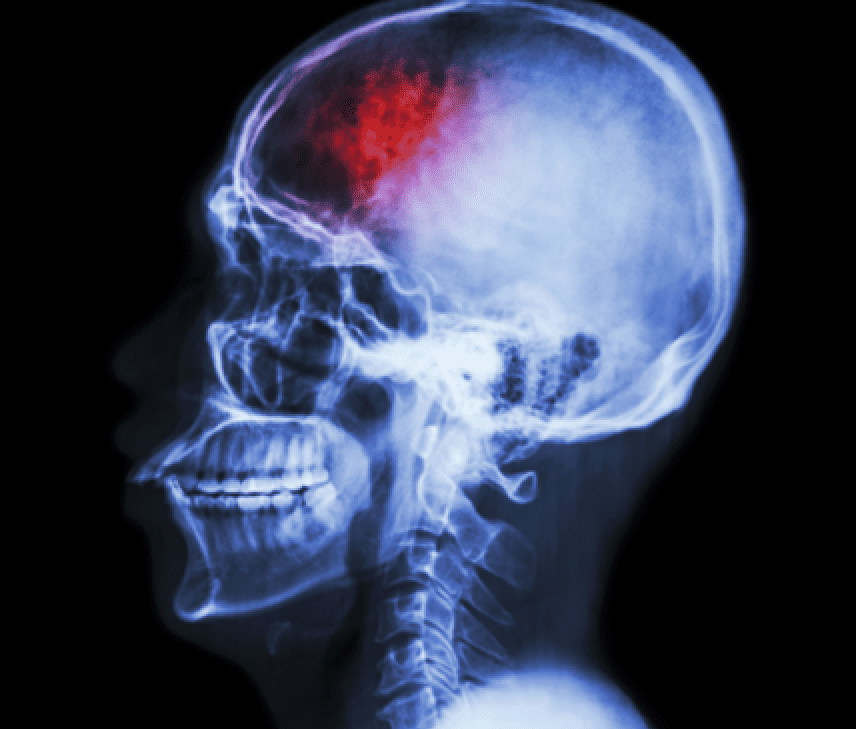

TBI can lead to motor deficits and chronic disability and currently there are no effective drugs to treat these deficits.

For the 20-minute procedure, a neurosurgeon drilled a tiny hole in the skull and, guided by MRI, injected the stem cells into the area of the lesion.